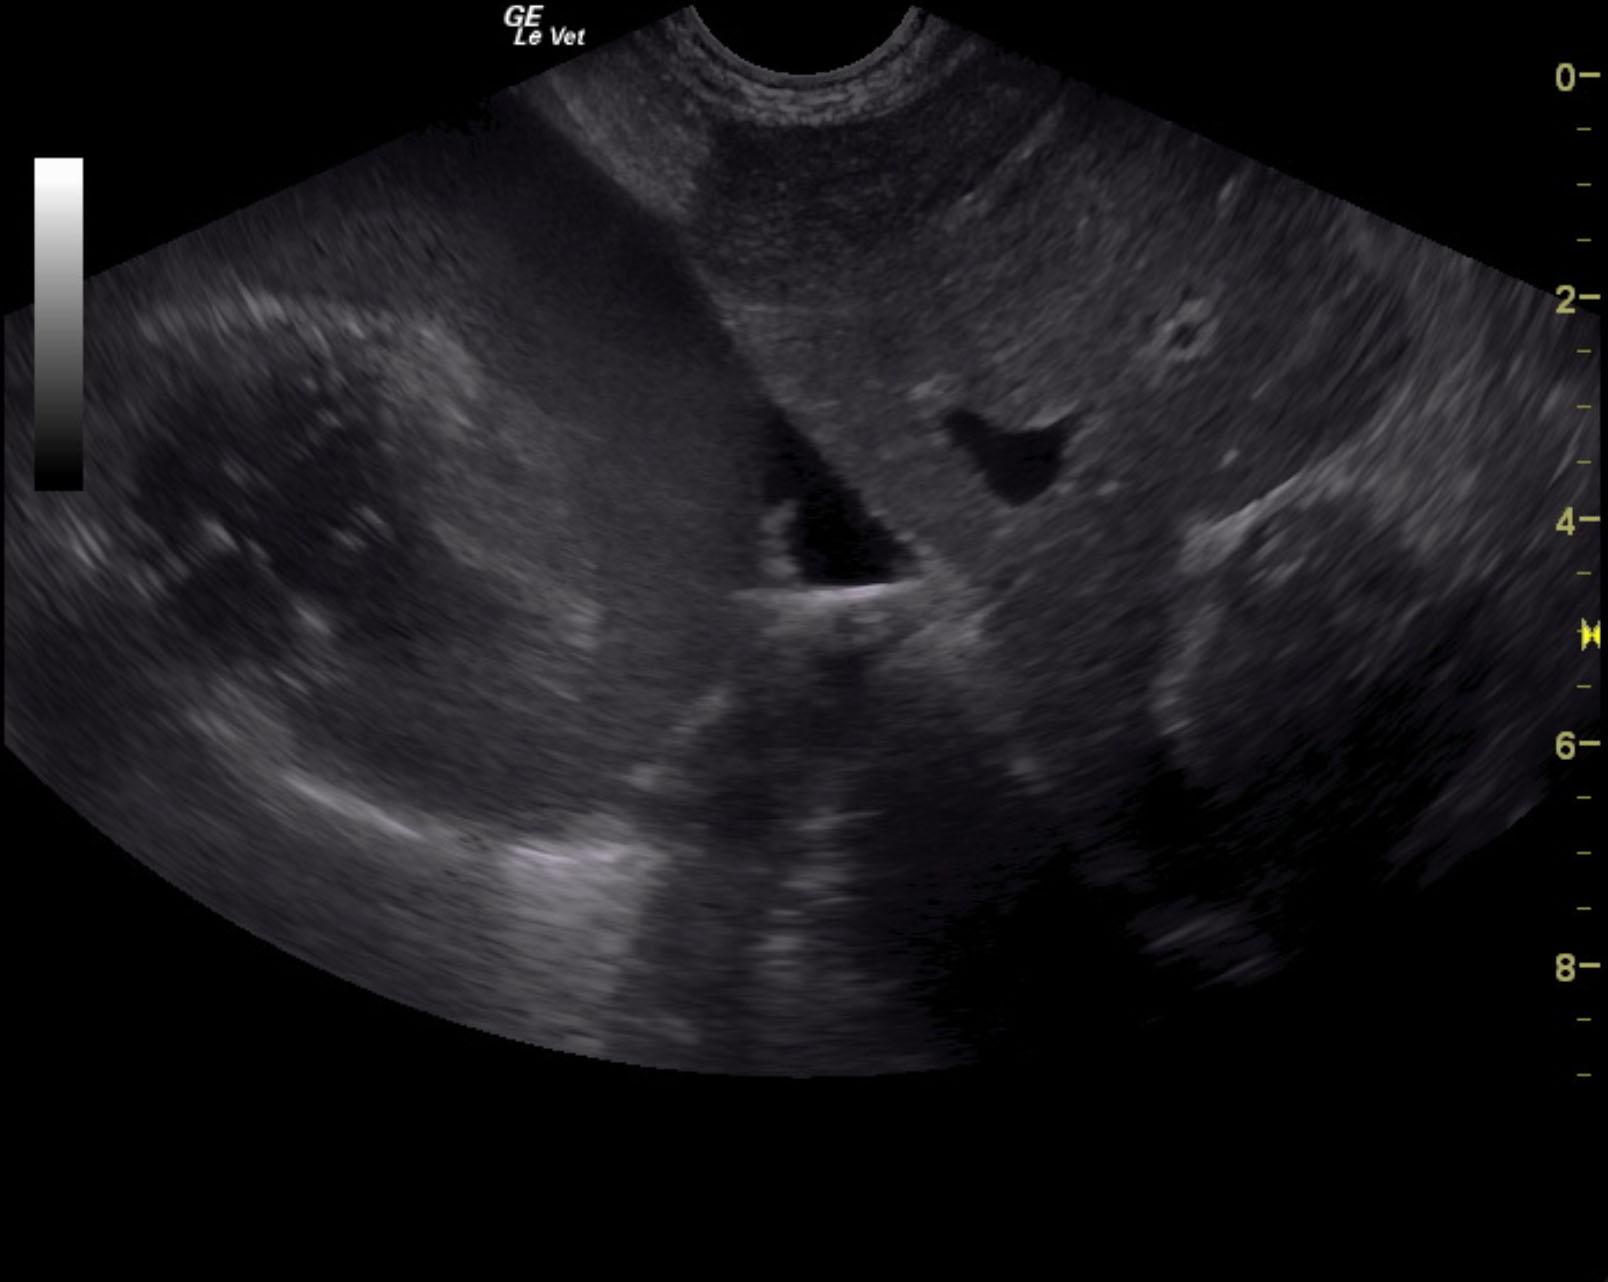

A 13-year-old NM Jack Russell terrier dog was presented for evaluation of PU/PD, decreased appetite, and abdominal distension. Blood work showed mild hypoproteinemia and elevated ALT activity.

A 13-year-old NM Jack Russell terrier dog was presented for evaluation of PU/PD, decreased appetite, and abdominal distension. Blood work showed mild hypoproteinemia and elevated ALT activity.